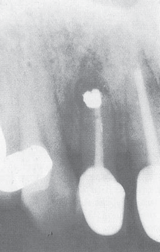

What material is this

Amalgam Retrograde Filling

•Presence of epical pathosis

•Removal of pathosis on the apical area

•Resealing the apical foramen with amalgam